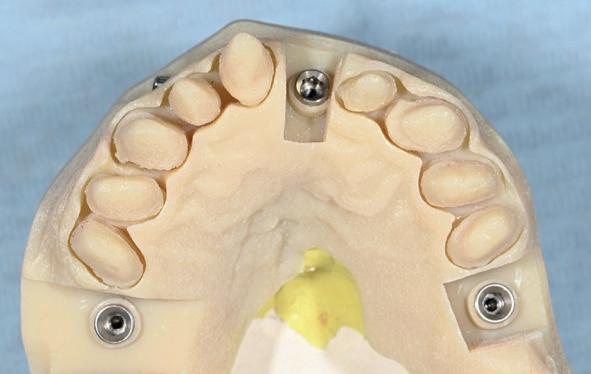

Ter beoordeling van het gewenste eindresultaat, werd een additieve wax-up vervaardigd. Deze werd met behulp van een siliconenmal en chemisch-hardende kunsthars omgezet in een intra-orale mockup (afbeelding 11). Ondanks de grove aard van deze voorlopige vormgeving bood deze voldoende diagnostische waarde om esthetiek en functie te beoordelen. Tevens faciliteerde de mock-up gedeelde besluitvorming tussen behandelaar en patiënt. Op basis van intra- en extraorale opnamen en een mondscan van de mock-up werd het ontwerp in overleg met het tandtechnisch laboratorium verder geoptimaliseerd (afbeelding 12).

Op basis van de digitale opstelling werd gestart met de restauratieve behandeling in de bovenkaak. Na

11. Mockup bovenkaak

13. Techniekmodel

plaatsing van de restauraties werden zowel de tandboog als de tandstand in de bovenkaak gecorrigeerd (afbeelding 13-15).